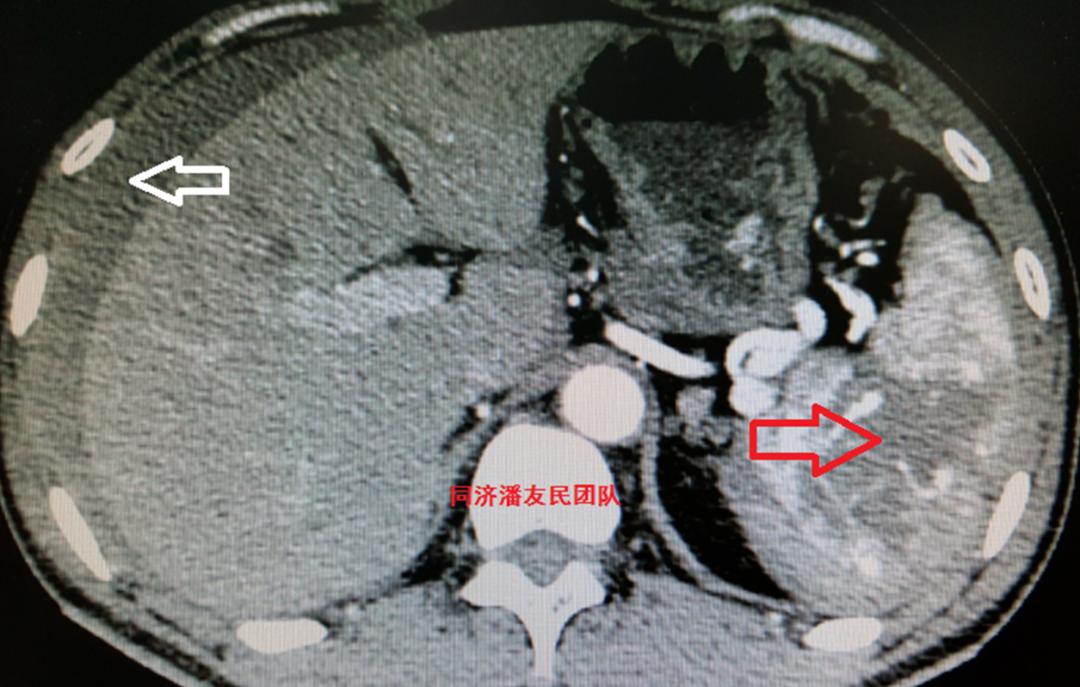

CTA同时发现脾脏破裂出血合并腹腔积液(图3)。

腹部彩超也证实脾破裂,腹腔积血(图4)。

心脏彩超、头部CT未见异常。初步诊断:车祸外伤、外伤性降主动脉夹层、脾破裂、失血性休克(早期)。